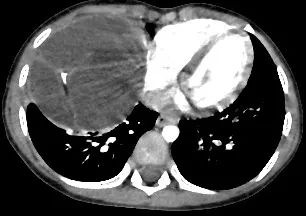

近日,广东医科大学附属医院胸外科主任医师梁克成功完成了一例切除巨大纵隔畸胎瘤的手术。患者是年仅4岁的孩子,因为持续高热、咳嗽和呕吐,在当地医院内科治疗后病情没有明显好转。于是家长带着孩子来到广东医科大学附属医院儿童医学中心,该中心副主任医师田川为孩子做了进一步的诊治,胸部CT结果显示前纵隔中下偏右侧见类圆形混杂密度影,内见分隔、钙化及脂肪样密度,大小约79mmX88mmX98mm,初步判断为畸胎瘤可能性大。

术前CT图像